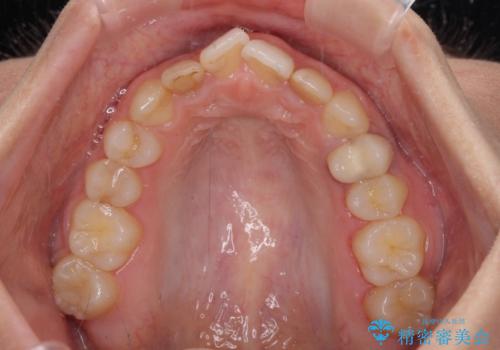

- 前歯の歯並びと神経を取って変色してしまった前歯を気にして来院された患者様です。

上下前歯の歯列不正はインビザラインにより整え、その後に、前歯2本をオールセラミッククラウンにて補綴治療することとしました。

下顎前歯が1本欠損しており、下顎歯列の大きさが本来よりも小さいため、上顎歯列とのバランスが悪く、深い咬み合わせになっていました。

上顎にIPRを多用して歯列の大きさを小さくするよう試みましたが、理想的な咬み合わせまでには改善させることはできませんでした。